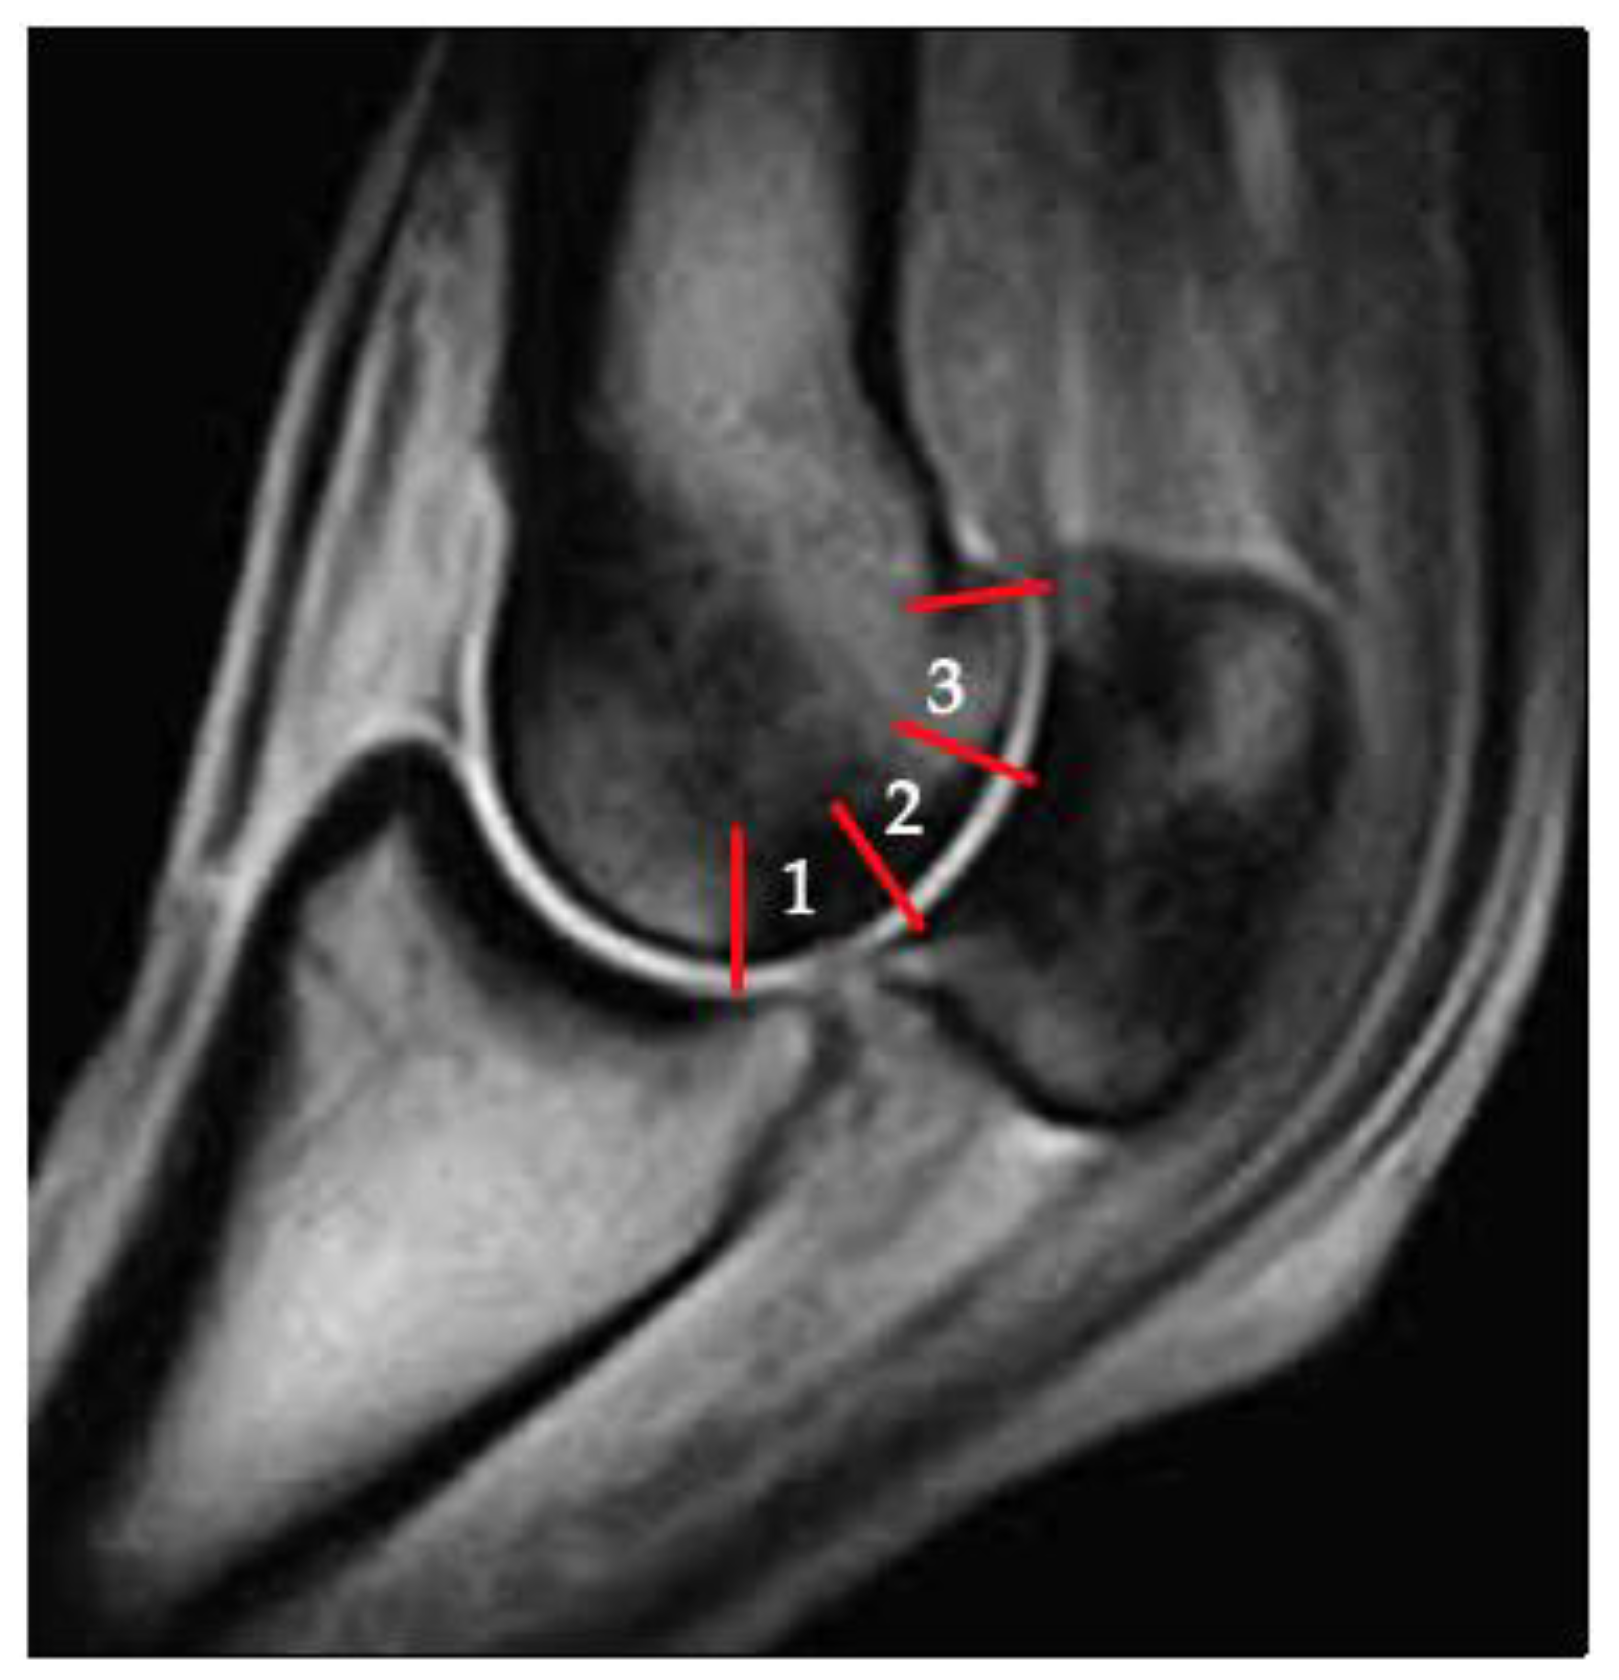

3.2. Sclerosis of the Subchondral and Adjacent Medullary Bone of the PSGs

3.3. PSG Subchondral Bone Lysis

3.4. PSG Subchondral Bone Defects